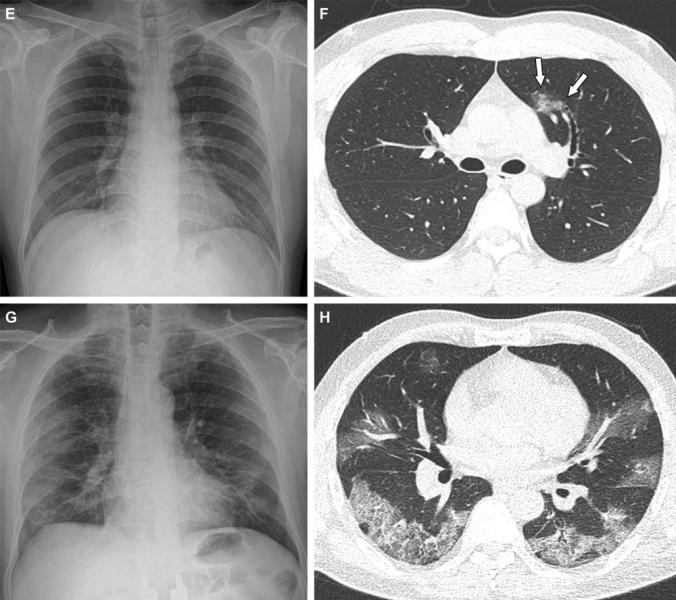

This photo gallery shows the variety of radiological presentations of COVID-19 (SARS-CoV-2) in medical imaging, including computed tomography (CT), radiograph X-rays, ultrasound, echocardiograms and magnetic resonance imaging (MRI). The radiology images show examples of typical COVID pneumonia in the lungs and the numerous complications the virus causes in the body in multiple organs, including the brain, kidneys, heart, abdomen and vascular system.